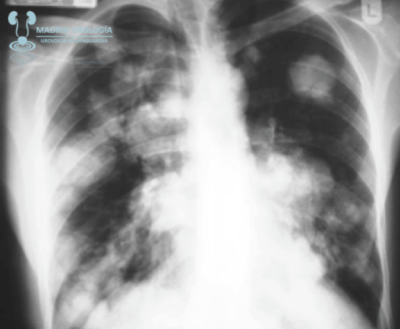

TAC TORAX

El TAC de tórax debe realizarse en todos lo casos de TCG No Seminomatoso y podría ser omitido en casos de TCG Seminomatoso sin afectación de metástasis infra diafragmáticas.

Según las guías de la EAU

El TAC de tórax se recomienda en todos los casos de TCG independientemente de la estirpe fundamentado en que un 10 % de los casos se presentan con nódulos subpleurales no detectables mediante radiológia simple.

El TAC de tórax tiene Alta Sensibilidad pero No Especificidad.

| Metástasis pulmonares en TAC. |